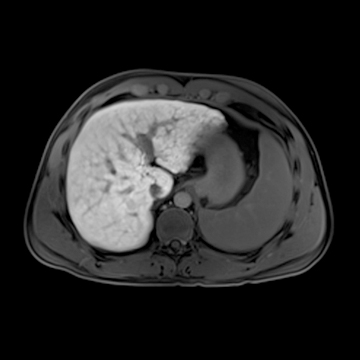

腹部造影検査

MRI画像(提供:シーメンスジャパン株式会社)